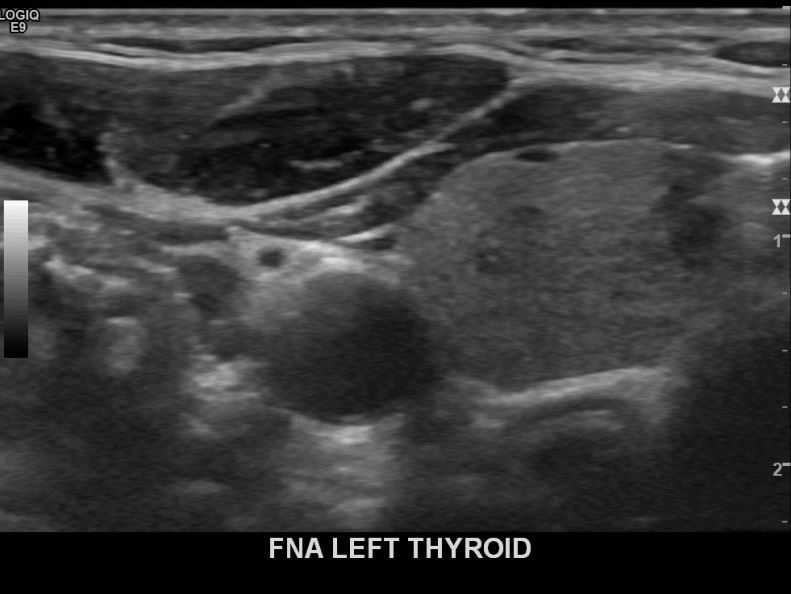

상기환자 외부검진이상으로 내원하신 40대중반 여성분으로 좌엽 의심스러운혹 세포검사진행후 갑상선암으로 진단되었습니다